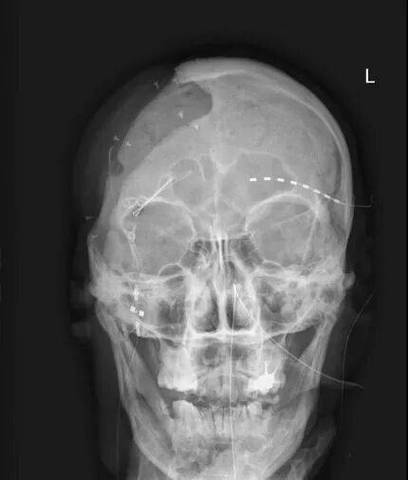

- 正中矢状面垂直于地面: 患者的头颅必须被摆放在一个位置,使得通过鼻根点(N)和蝶鞍点(S)的连线(NS线)与地面垂直,这意味着患者的头颅左右两侧完全对称地位于X光束中。

- 眶点(Orbitale, Or)与耳点(Po)水平对齐: 在侧位片上,眶点(Or,眼眶最下点)和耳点(Po)应位于同一水平线上,这确保了颅底平面(Frankfort Horizontal Plane, FH平面)在影像中是水平的。

- 头颅左右两侧是否对称?下颌骨升支、髁突、颧弓等结构是否双侧对称显示?

- 头部倾斜(歪头): 导致正中矢状面不垂直,左右结构不对称,所有角度测量(如ANB角)和距离测量出现偏差。

- 鼻根点(N)未居中: 导致头颅影像在探测器上偏移,可能影响部分结构的显示和测量范围。